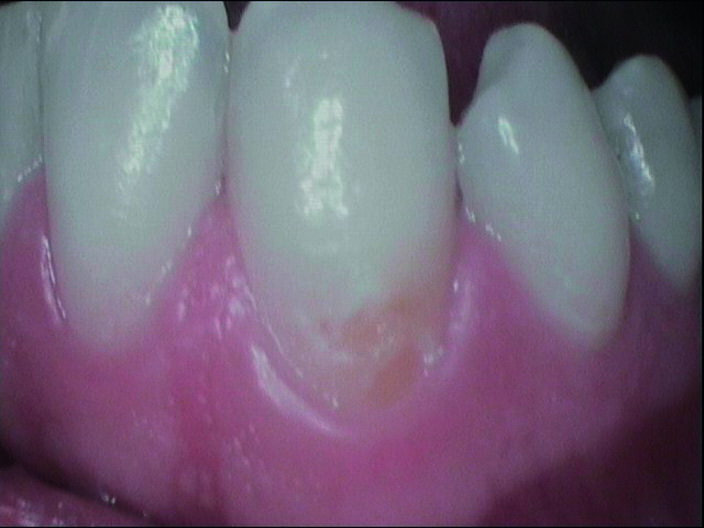

Durante l’esame obiettivo (Figg. 1a, 1b) rileviamo il danno iatrogeno da terapia ortodontica precedente alla visita e riscontriamo la presenza di processo carioso ICDAS 3 in zona 33 e in zona 47, white spots in zona 31 e 41. Durante l’esame obiettivo, l’ausilio della videocamera intraorale Sopro-Care (Acteon) permette, tramite filtri appositi, di evidenziare in modo rapido e accurato le zone di demineralizzazione e le aree infiammate e di mostrarle al paziente in real time, rendendolo attivamente partecipe e consapevole della situazione clinica (Figg. 2a-2f). I ricercatori del Baylor College of Dentistry hanno dimostrato che il 23,4% dei pazienti ha sviluppato almeno una white spot lesion durante il trattamento ortodontico.